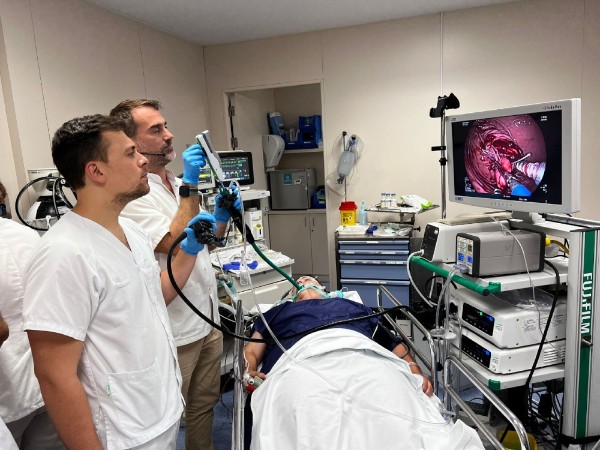

El Instituto del Aparato Digestivo Teknon lanza una técnica innovadora para el tratamiento de la obesidad

La técnica endoscópica MEGA es una evolución de la endomanga que permite realizar con menos sutura una mayor reducción del estómago.